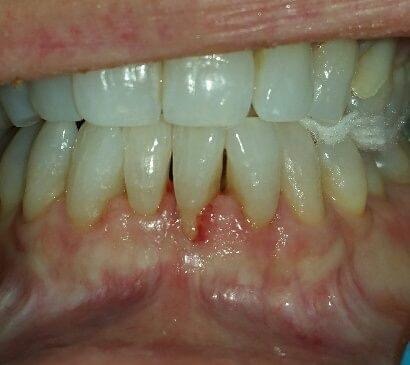

What is gum recession? Gum recession refers to the loss of gum tissue along the gumline. This can occur as a result of periodontal disease (gingivitis, periodontitis, advanced periodontitis), the natural aging process, or abrasive habits when it comes to brushing the teeth.

Why should gum recession be taken seriously? When gum recession occurs, the root structure of the tooth becomes exposed. This means that tooth decay and other problems can affect the teeth along the gumline and beneath it. Since healthy gums are essential for a healthy mouth, getting gum recession treated is important for lasting dental wellness.

BEFORE AND AFTER PICTURES: